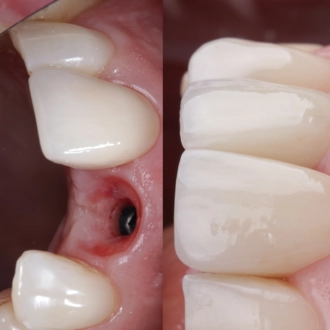

Хирургический этап проходит под местной анестезией или в условиях медикаментозного сна. После надреза десны и обнажения челюстной кости в месте имплантации стоматолог выполняет остеотомию (отверстие для имплантата) с помощью сверл разного диаметра, постепенно расширяя место имплантации. Окончательное остеотомическое отверстие соответствует толщине и длине имплантата, который будет в него установлен. Имплантат фиксируется в кости, после чего происходит ушивание зоны вмешательства.

При немедленной одноэтапной процедуре имплантат устанавливается в кость сразу после удаления зуба, а на абатмент имплантата устанавливается временная коронка. Временная коронка заменяется на фарфоровую коронку после периода полного приживления имплантата. Этот вариант процедуры является менее травматичным для костной ткани и имеет значительно меньший период восстановления. Врачи РЕФЕРТА в совершенстве владеют этой методикой, благодаря чему наши пациенты значительно сокращают свой путь к заветной улыбке.

В случае, когда имплантация выполняется по стандартной методике в два этапа процедура будет в первую очередь отличаться сроками восстановления. После остеотомии происходит установка имплантата с ушиванием окружающих тканей. После этого пациент ожидает заживления тканей и приживления имплантата (остеоинтеграция длится в среднем до 10 недель) и только после этого переходит к этапу установки коронки.